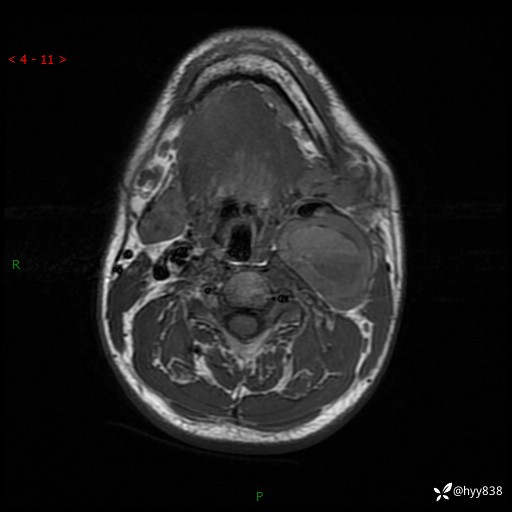

年轻小伙,发现左侧颈部肿物3年余,逐渐增大---结果公布~

现病史:患者约3年前因感冒发现左侧颈部长一肿物,约半个鸡蛋大小,无明显疼痛及其他不适,一直未行特殊处理。3个月前发现左侧颈部肿物变大,随后至当地市第二人民医院耳鼻喉科行左侧颈部彩超示:左侧颈部囊实混合性包块;喉部MPR示:左侧胸锁乳突肌内前方占位,累及左侧喉旁间隙,建议增强扫描。建议手术治疗。患者考虑。随后至我院肿瘤科就诊,行细胞学穿刺示:考虑血管源性肿瘤可能,建议进一步检查。建议至我院口腔科就诊,行颌面部MRI示:左侧颌下腺后方团状异常信号灶,建议增强。建议手术治疗。为求进一步治疗,门诊以“左侧颈部肿物”收入院。 起病以来,患者神志清、精神良好,饮食睡眠良好,大小便正常,体重未见明显变化。

颈部MRI平扫+增强